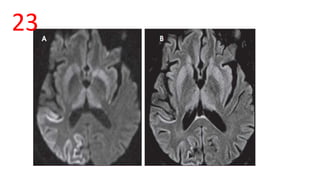

HOCKEY STICK SIGN

• DWI and FLAIR images – symmetrical pulvinar hyperintensities

• Characteristic of variant CJD

HOCKEY STICK SIGN •DWI and FLAIR images – symmetrical pulvinar hyperintensities • Characteristic of variant CJD